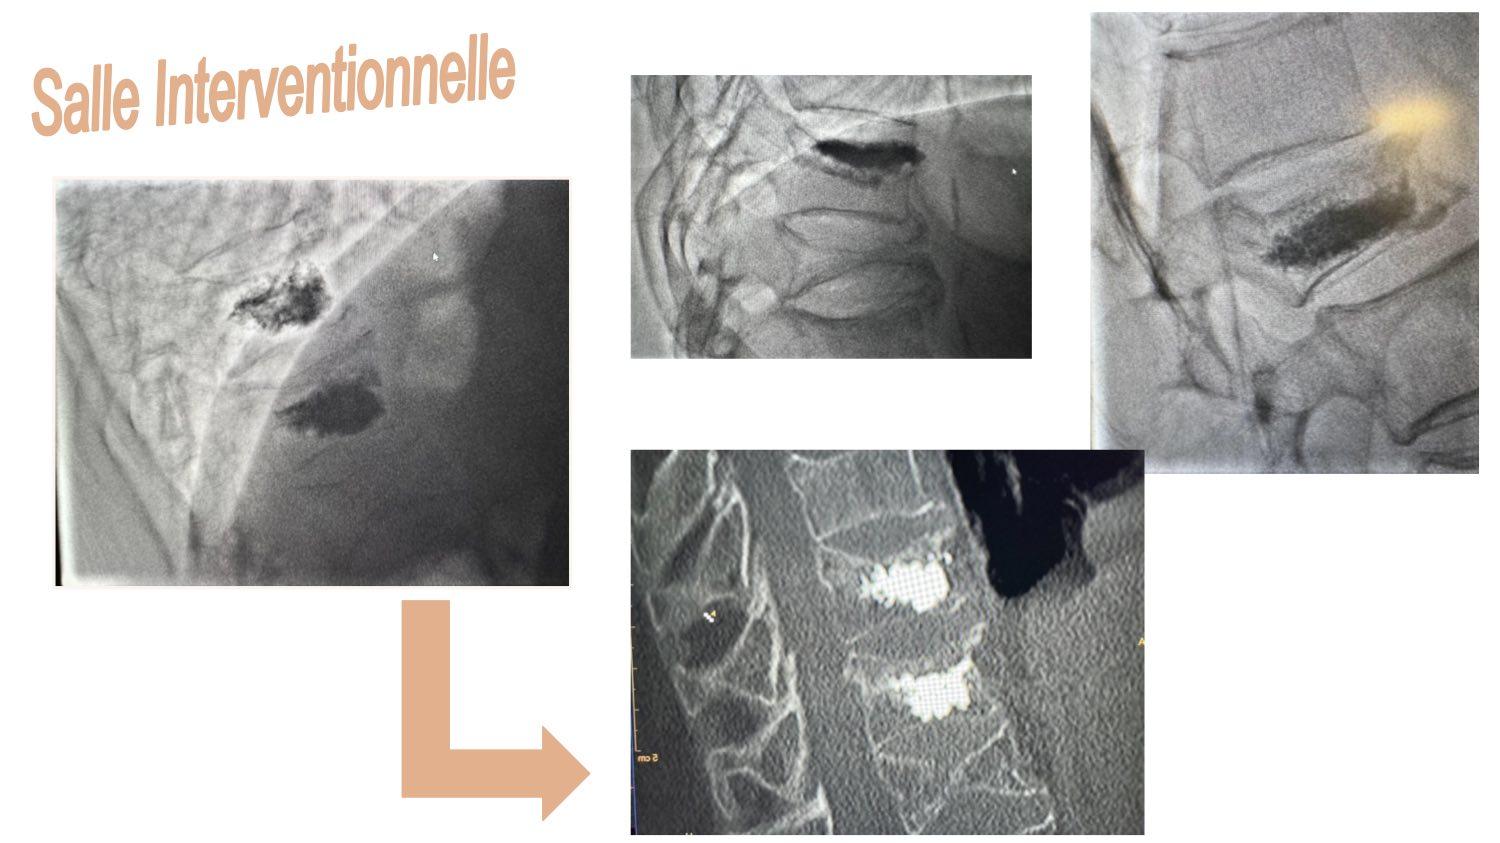

La Cimentoplastie pour le Généraliste

Dr Olivier VANAERDE